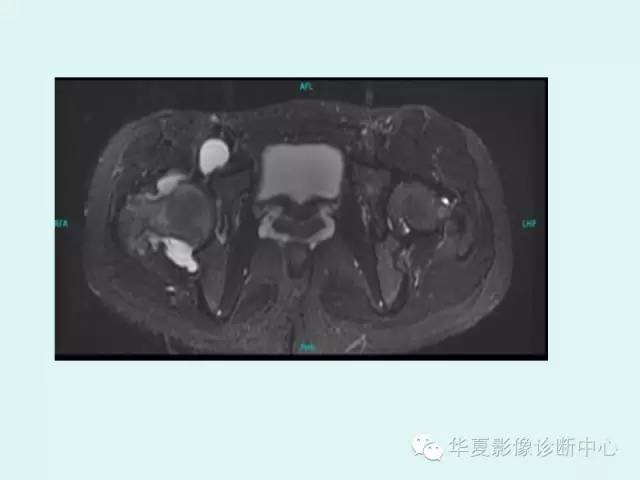

【PPT】大转子周围滑囊炎